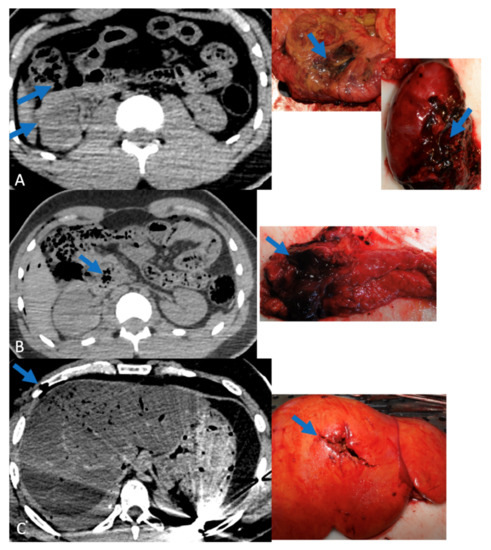

Figure 1, Figure 2 and Figure 3 show correlations between CT scan data and autopsy photographs.

Figure 1. Correlations between CT scan and autopsy concerning cephalic lesions (arrows) (A) left temporal lobe lesion, (B) left subdural hematoma.